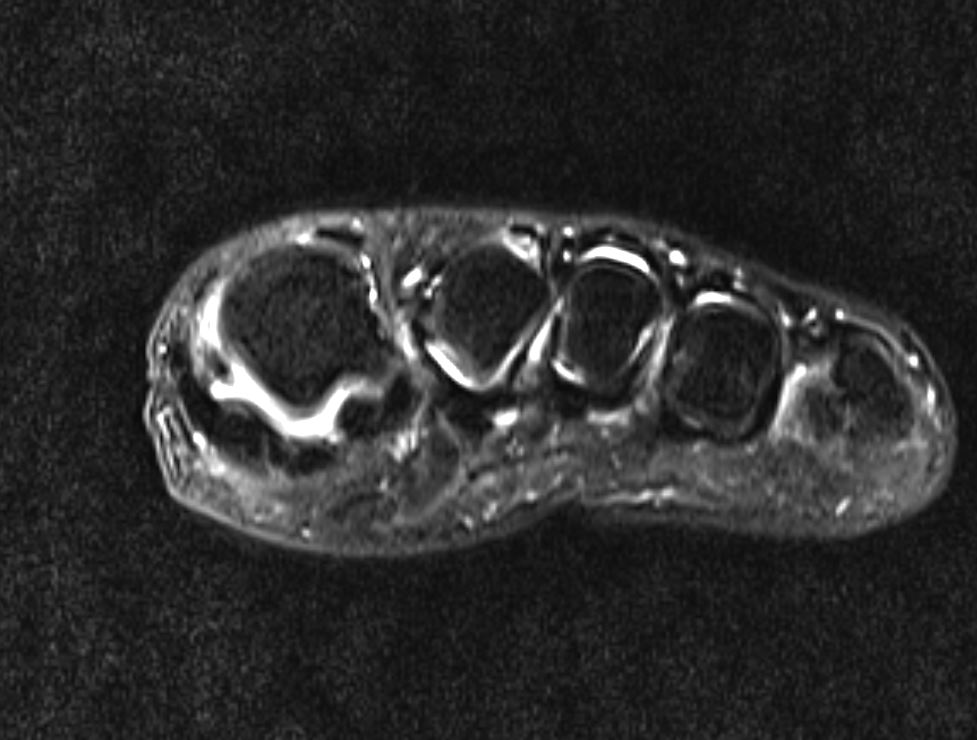

Home Schwerpunkte Krankheitsbilder Turf Toe Verletzung des Großzehengrundgelenks Turf Toe MRT alter knöcherner Kapselausriss

Turf Toe MRT alter knöcherner Kapselausriss